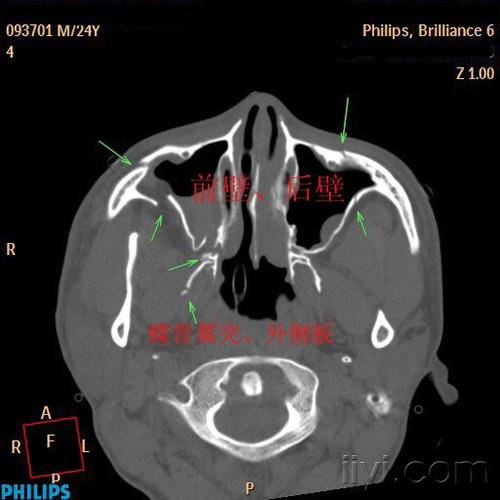

上颌窦外侧壁层面

上颌窦分几个壁ct图

上颌窦ct解剖图

上颌窦ct解剖示意图